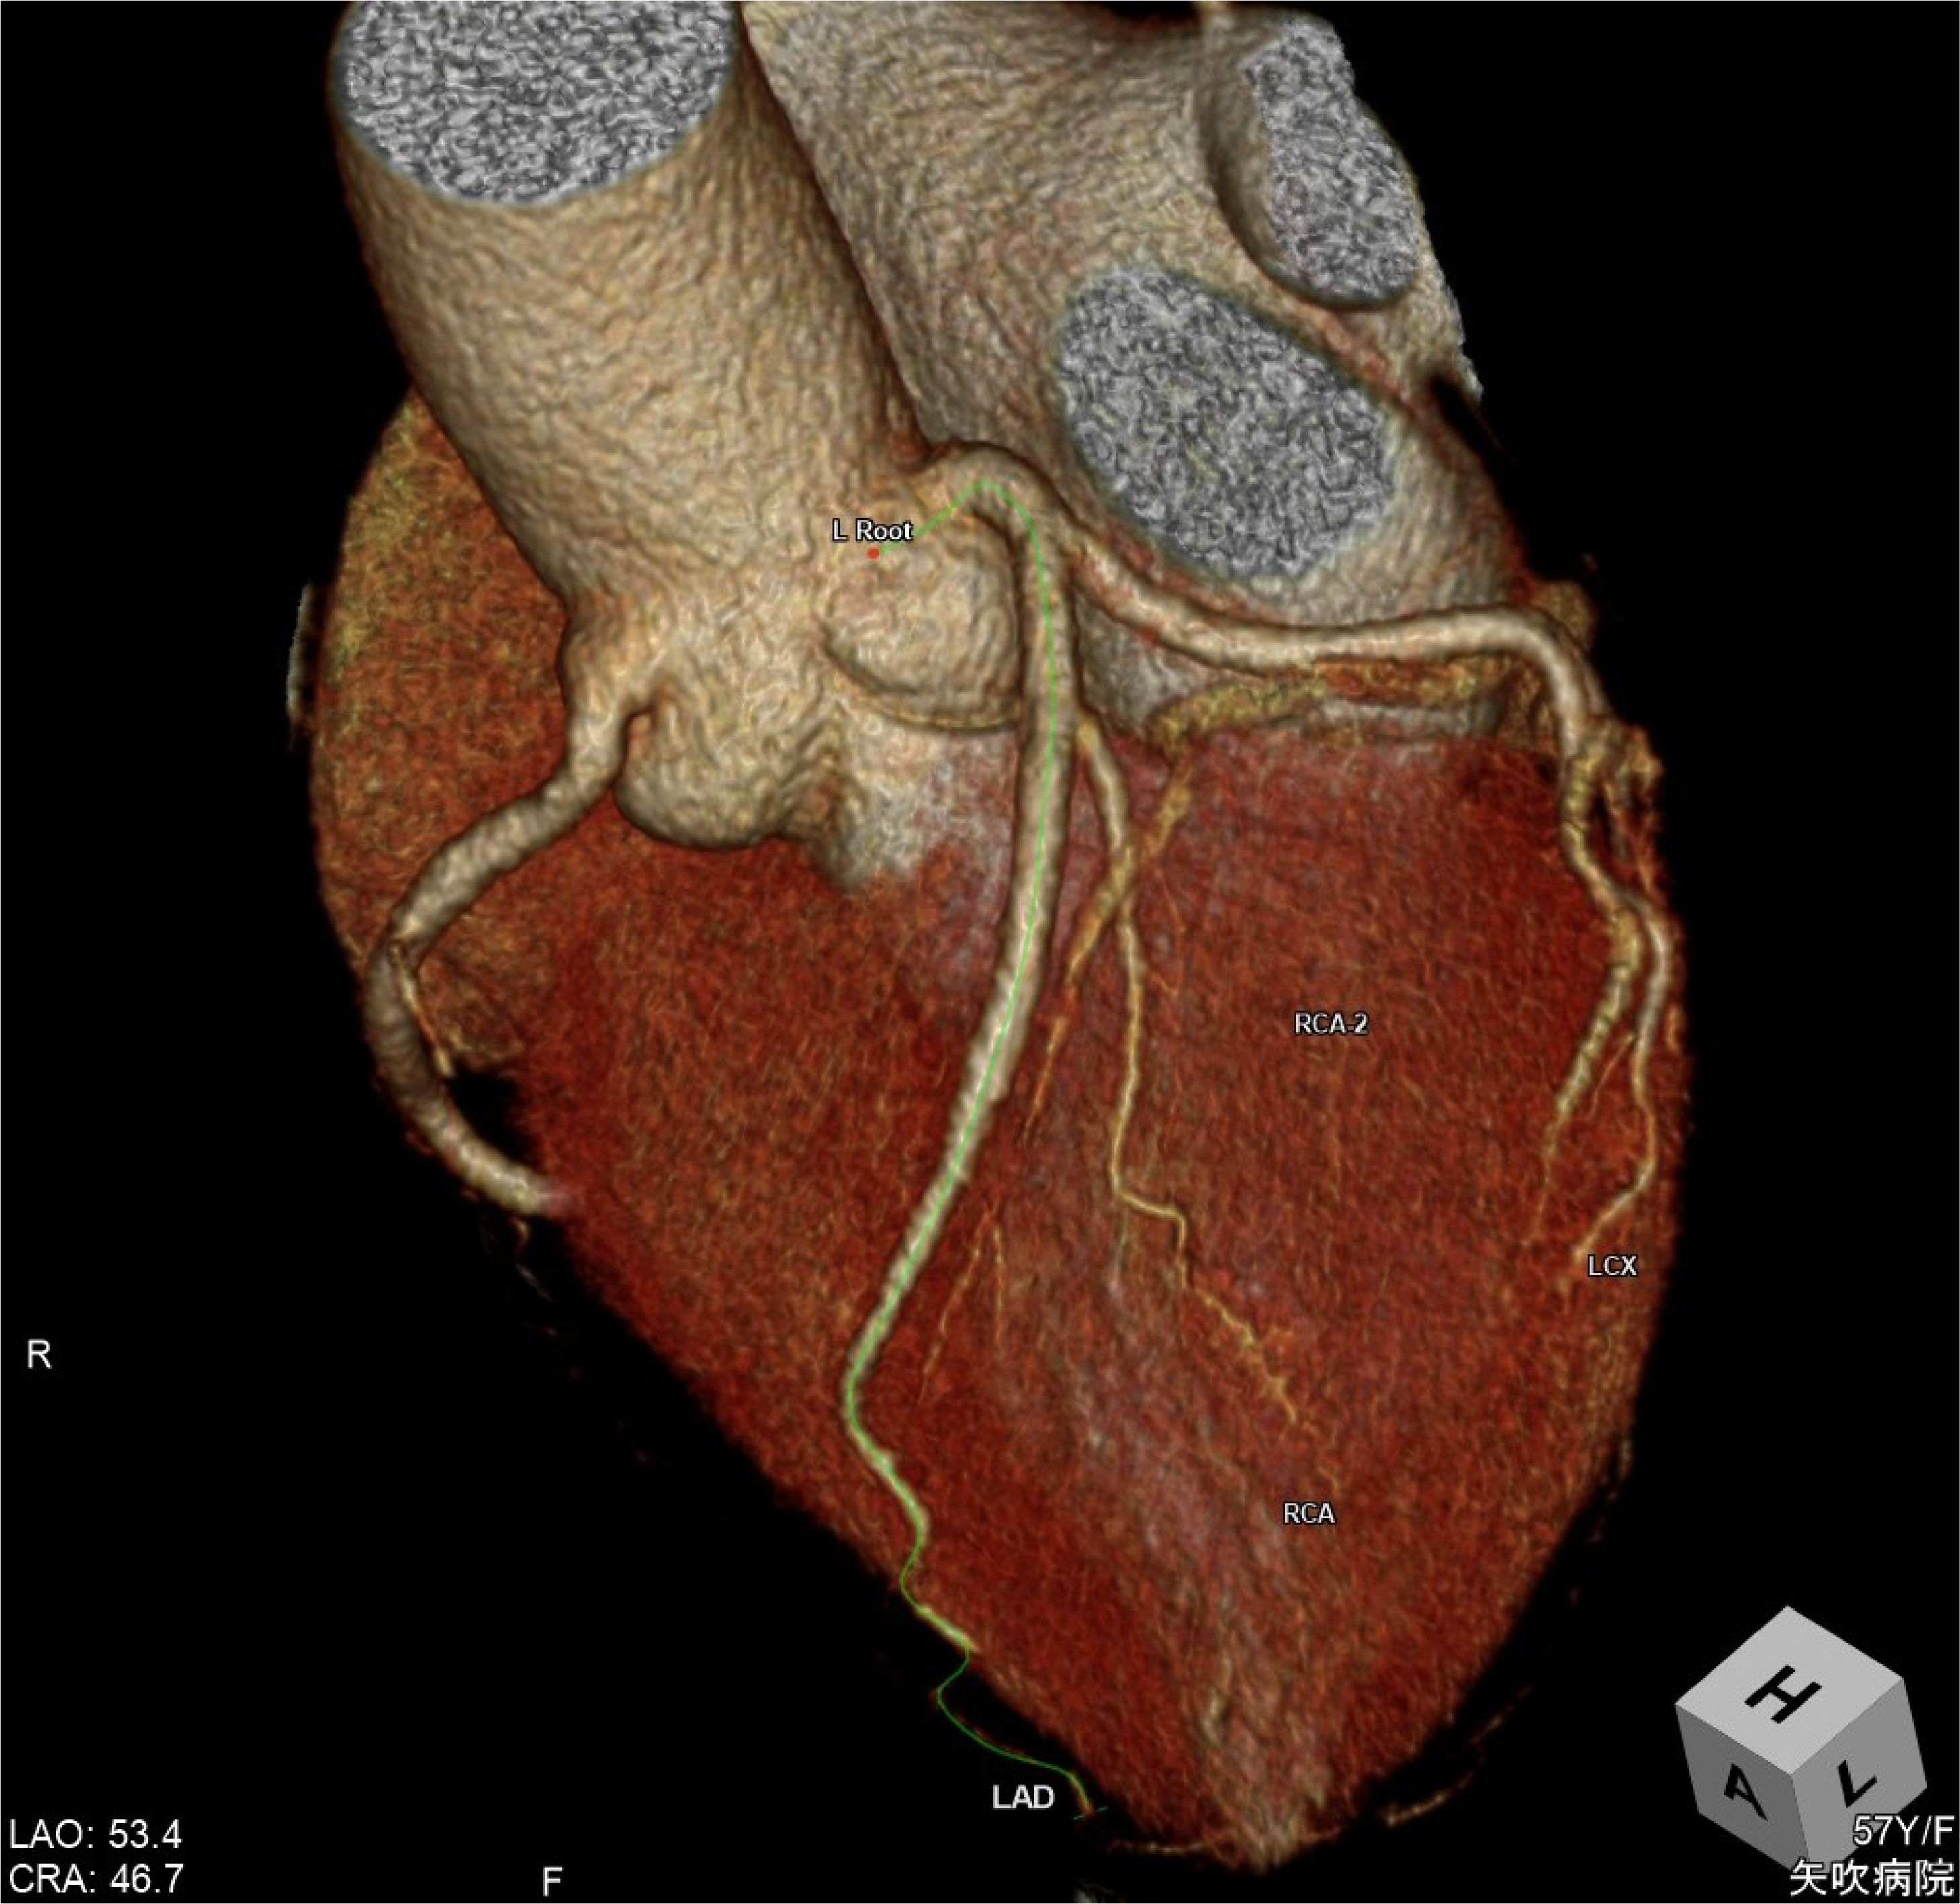

CANON(旧:東芝)社製の80列マルチスライスCTを設置し、胸部・腹部の撮影はもちろん、心臓CTや大腸CT、下肢3DCTといった専門性の高い撮影も行っています。最新のザイオワークステーションを用いて、3D画像作成、心臓解析、大腸の仮想内視鏡検査などを行っています。また、近隣の医療施設からのCT撮影依頼にも対応しており、日々たくさんご利用いただいております。被ばく線量の低減に配慮するとともに、患者さんに合った適切な線量で撮影を行うように心がけています。

心臓CT画像 大腸CT画像